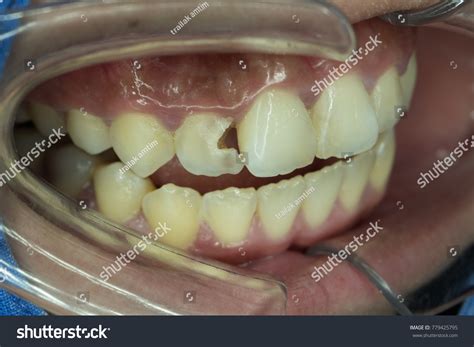

• Discoloration or darkening of the tooth.

A major concern for patients is whether a root canal on front tooth will cause the tooth to turn dark or gray over time. While this can happen due to internal debris or the material used, modern techniques have significantly reduced the risk. If color changes do occur, your dentist can suggest cosmetic solutions such as internal bleaching, porcelain veneers, or a crown to match your natural tooth shade.